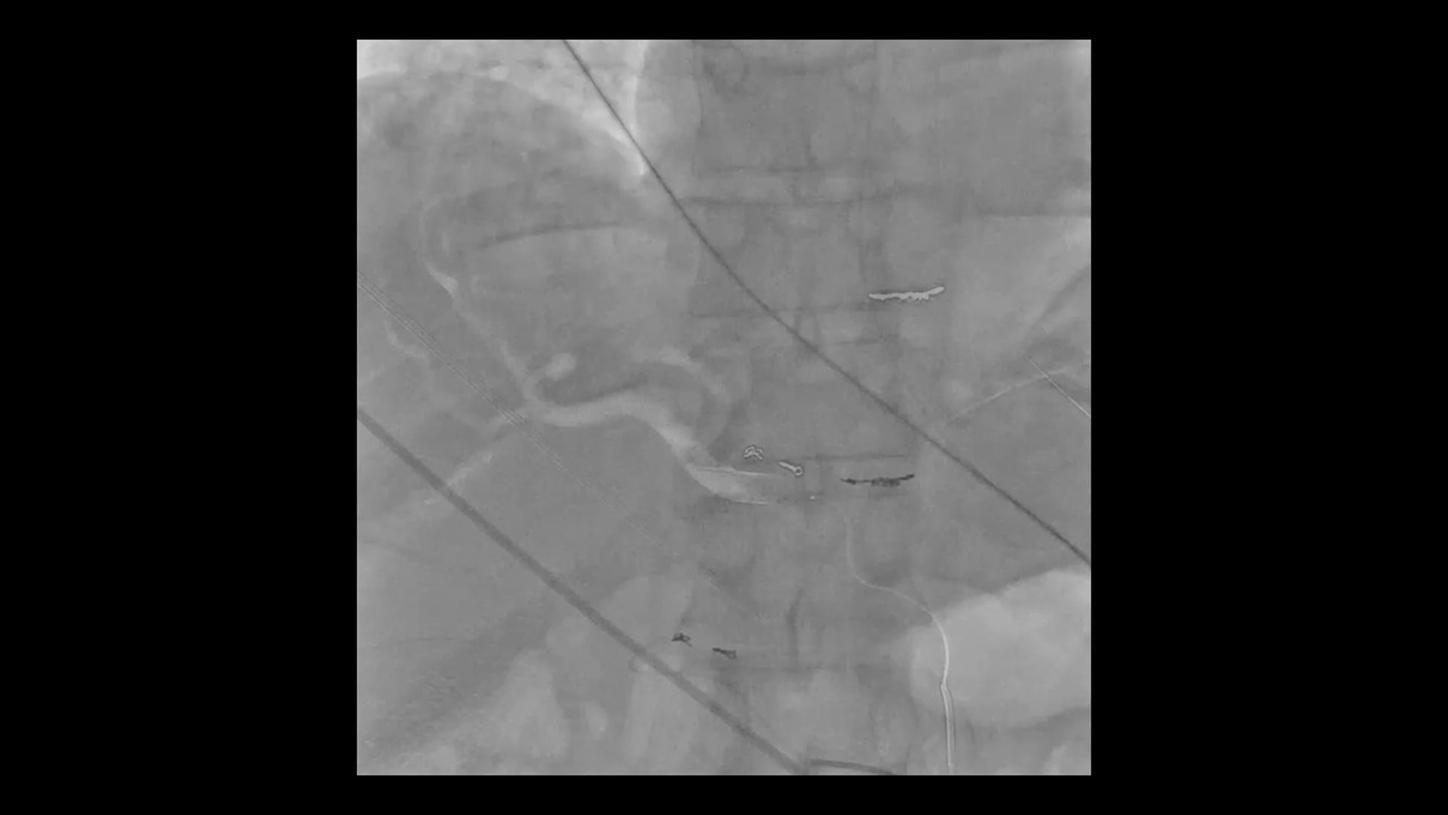

During minimally invasive procedures, it is critical to have a clear view of anatomies and devices. Yet complex imaging tasks or challenging patient conditions often impact image quality. OPTIQ AI delivers constant image quality1 defined by CNR in support of the ALARA principle, independent of patient or C-arm angulation. On top, an AI-powered algorithm reduces image noise in real time across different 2D imaging modes.

Make AI-powered imaging and clear insights your standard during interventions – with OPTIQ AI.